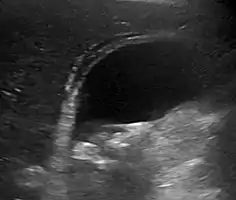

Right upper quadrant abdominal ultrasound is most commonly used to diagnose cholecystitis.[1][25][26] Ultrasound findings suggestive of acute cholecystitis include gallstones, pericholecystic fluid (fluid surrounding the gallbladder), gallbladder wall thickening (wall thickness over 3 mm),[27] dilation of the bile duct, and sonographic Murphy's sign.[13] Given its higher sensitivity, hepatic iminodiacetic acid (HIDA) scan can be used if ultrasound is not diagnostic.[13][14] CT scan may also be used if complications such as perforation or gangrene are suspected.[14]

Gallstones and biliary sludge, but the gallbladder wall is not clearly thickened, with no edema in the pericholecystic fat, thus not cholecystitis.